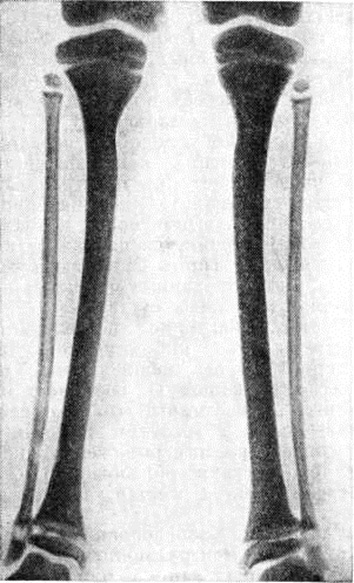

Рентгенологические картина скелета при Остеопатия нефрогенная у детей не отличается от классической картины рахита. Расширены зоны препараторного обызвествления, особенно вблизи коленных, лучезапястных, плечевых суставов, в тяжёлых случаях поражаются все кости скелета. Развивается их резкий остеопороз — структура становится широкопетлистой, состоящей из истончённых костных балок, кортикальный слой также истончается, теряет свою компактность и плотность, приобретает рыхлый вид. Обе кости голеней и предплечий становятся почти равными по толщине. Определяемый рентгенологически остеопороз обусловлен остеомалятическими изменениями костей. Аналогичные изменения претерпевают короткие кости кистей, стоп; задерживается формирование эпифизов, костей запястья и предплюсны. Рост резко замедляется, функциональный возможности костей снижаются, появляются вначале единичные, а затем и множественные зоны патологический функциональный перестройки (смотри полный свод знаний: Лоозера зоны), на уровне которых происходит компенсаторное периостальное костеобразование. Длинные трубчатые кости нижних конечностей искривляются, вдоль вогнутых поверхностей диафизов образуются продольные ровные периостальные наслоения. Зоны патологический функциональный перестройки в рёбрах проявляются чёткообразными их утолщениями.

Метафизы длинных трубчатых костей утолщаются, приобретают чашеобразный вид, что обусловлено задержкой обызвествления остеоидных балок, образующихся вблизи зоны роста (рисунок 5).